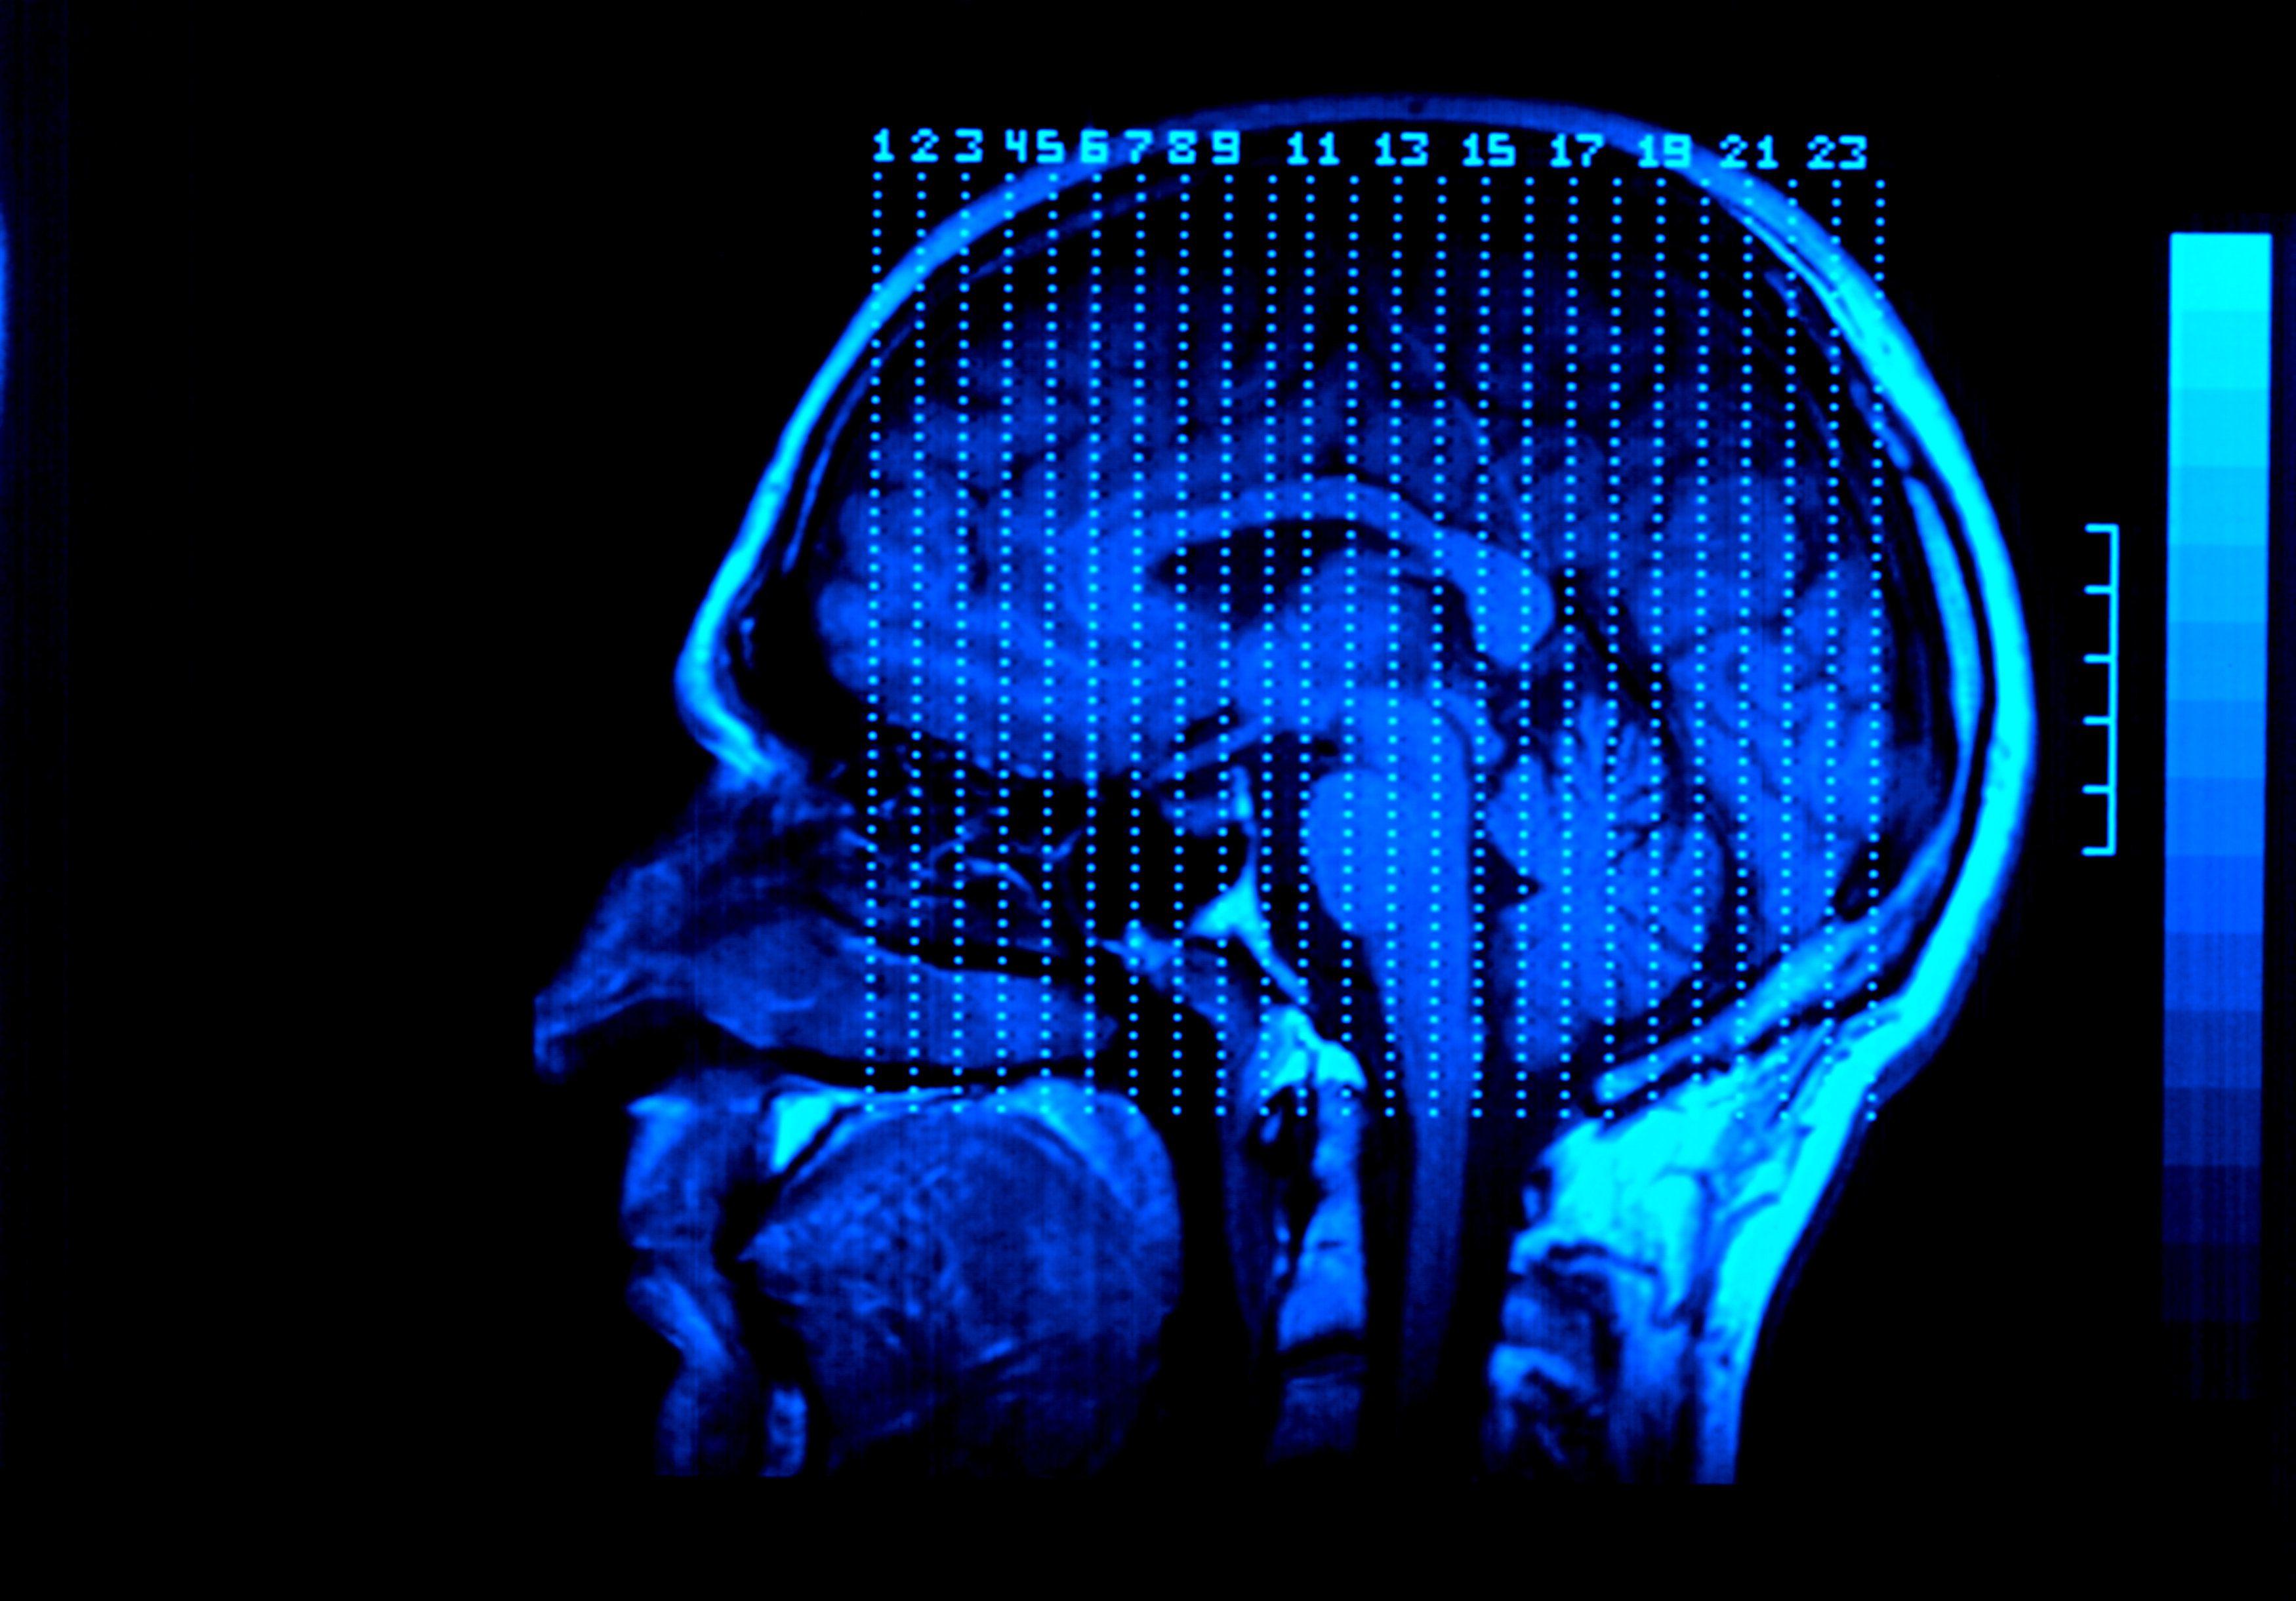

(Natural News) Le mois dernier, au cours d'une session de l'International Crimes Investigative Committee (ICIC), l'avocat Dr. Reiner Fuellmich a interviewé le Prof. Sucharit Bhakdi, le Prof. L'un des sujets abordés est la façon dont les injections endommagent les petits capillaires du cerveau, passent outre la barrière hémato-encéphalique et provoquent des dommages cérébraux importants qui entraînent souvent des changements de personnalité extrêmes.

Wolf a expliqué qu'elle avait elle aussi remarqué ce phénomène. Et il y a des raisons à cela qui, selon Bhakdi, sont dues à la rupture de la barrière hémato-encéphalique et à l'insertion d'ARNm dans le tissu cérébral. Et le plan, a révélé Bhakdi dans plusieurs présentations qu'il a données, est de faire en sorte que tous les "vaccins" contiennent de l'ARNm.

Les dommages que cela cause au système nerveux sont quelque chose qui peut être mesuré et observé de manière tangible, ce que la discussion met en évidence. Les personnes qui se sont fait piquer ne sont plus elles-mêmes, et dans de nombreux cas, elles expriment des émotions inhabituelles qui ne faisaient pas partie de ce qu'elles étaient avant les injections.